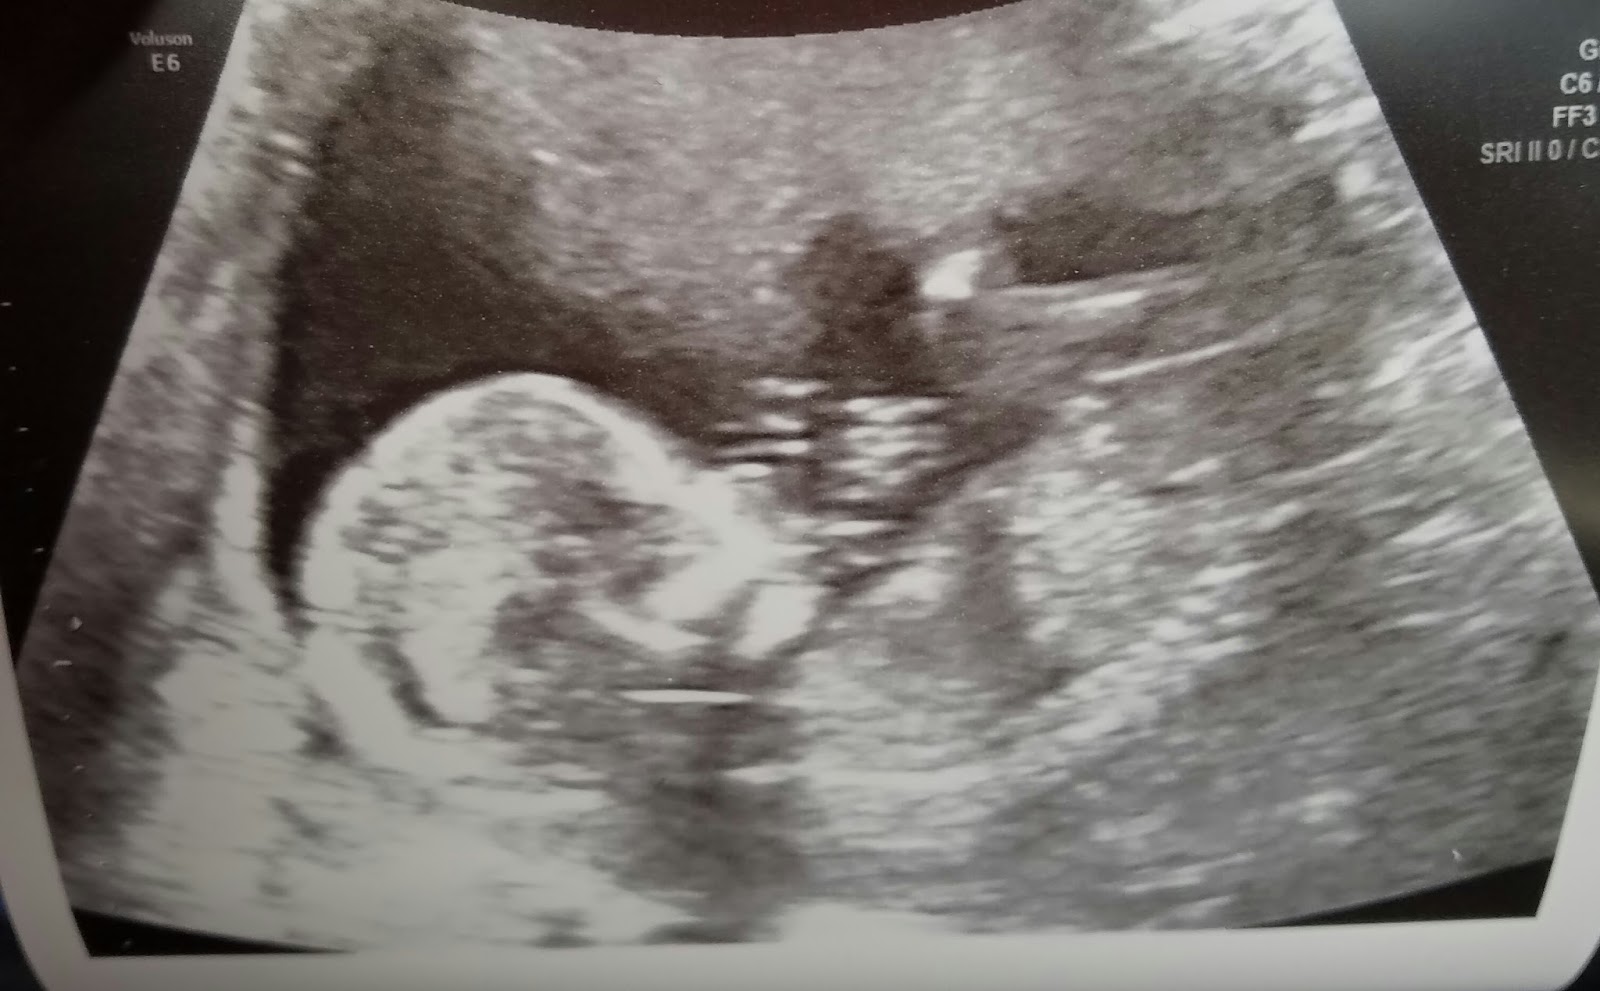

I've had three ultrasounds so far. Or is it four? In any case, here's what the little bugger looks like, or looked like at 16 weeks. Cutie pie.

I think there's a similarity to Indigo's ultrasound from the same week. What do you think?

Hard to tell, I know. But he doesn't really resemble Periwinkle, right?